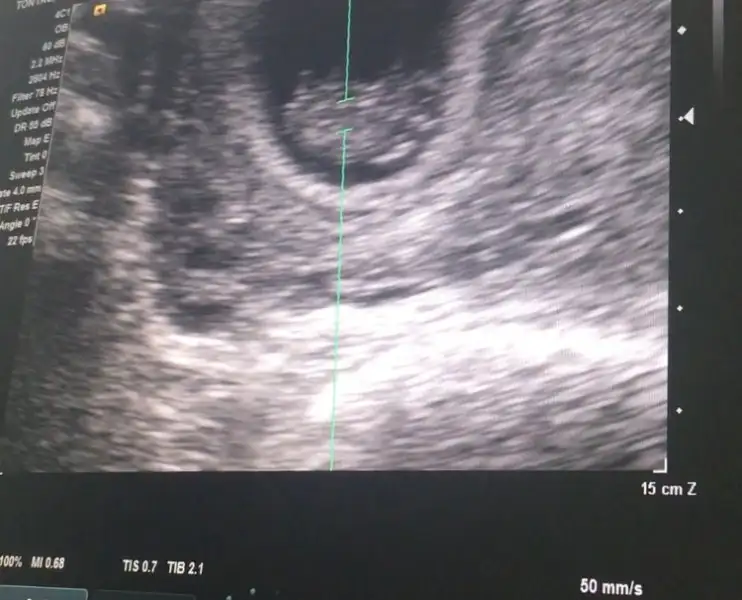

Doktor,detayli tahlil, mide bulantısı derken biraz zaman geçti ve 9.hafta içindeyim..